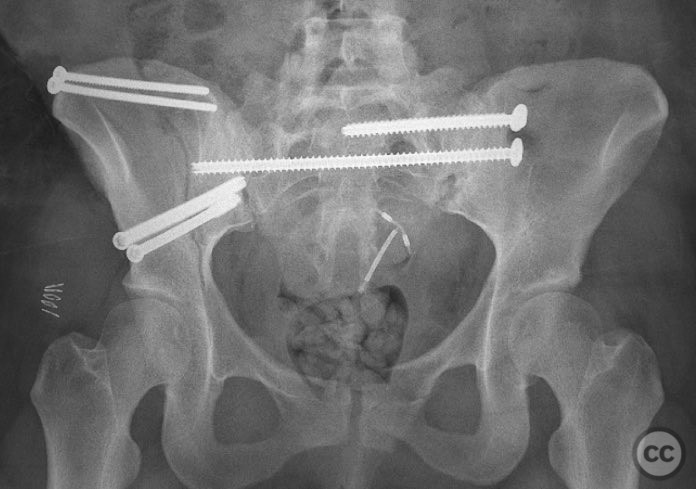

Percutaneous Iliosacral and Anterior Iliac Screw Fixation for AO/OTA 61-B2 Pelvic Ring Injury

Clinical Details

Clinical and radiological findings:  A 26-year-old female sustained a closed pelvic ring injury following a motor vehicle accident. She was hemodynamically stable, neurologically intact, and had no other associated injuries. Skin integrity was preserved. Initial management included pelvic binder application and 10 pounds of distal femoral skeletal traction. Portable AP pelvic radiograph demonstrated a left-sided sacral fracture with associated ipsilateral iliac wing and pubic ramus fractures, consistent with an AO/OTA 61-B2 (lateral compression type II) injury pattern.

Anatomical surgical approach:  The left sacral fracture was addressed first via percutaneous placement of iliosacral screws under fluoroscopic guidance. An anterior approach to the iliac wing was performed via a longitudinal incision along the crista iliaca, subperiosteal dissection to expose the fractura alae ossis ilii, followed by debridement, reduction, and temporary clamping. Definitive fixation was achieved with two 7mm diameter cannulated fully threaded medullary screws placed across the iliac crest and pelvic brim into the corpus ossis ilii. The left ramus ossis pubis fracture and overall cingulum pelvicum were assessed intraoperatively with fluoroscopy for residual instability.

Intraoperatively, minimal residual deformity of the left hemipelvis was noted after traction and positioning. The sacral fracture was stabilized first with iliosacral screws. The anterior iliac exposure allowed for direct visualization, cleaning, reduction, and clamping of the iliac wing fracture prior to screw fixation. After fixation, intraoperative fluoroscopic stress examination demonstrated stability of the left pubic ramus fracture and overall pelvic ring, obviating the need for further anterior fixation.

Orthopaedic implants used:   Two 7mm diameter cannulated fully threaded medullary screws (iliac crest and pelvic brim), percutaneous iliosacral screw(s).